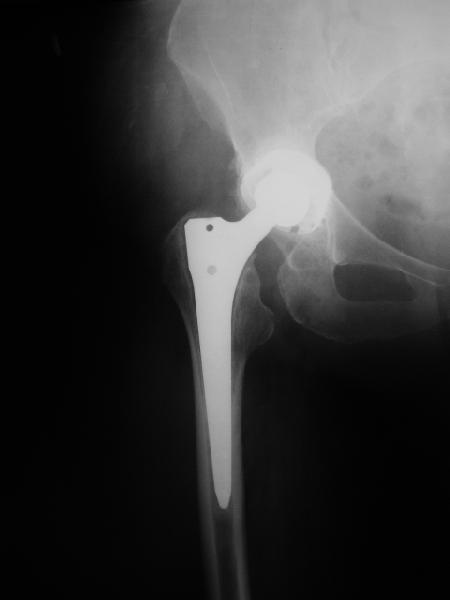

24 апреля 2005 г. правый сустав фас (тут и болит)

С выбором имплантата можно не согласиться, но скорее всего просто поставили то, что было в наличии. :( Вертлужный компонент установлен

слишком медиально. По представленным рентгенограммам нельзя исключить нарушение целостности дна вертлужной впадины. Даже если в данным момент нестабильности нет, то она обязательно возникнет и скорее всего, создаст

На представленных Р-граммах явных признаков нестабильности эндопротеза нет. Чашка хоть и медиализирована, но стоит так же, как и 3 года назад и остеолиза нет. Есть остеолиз вокруг проксималного отдела ножки, но линия тонкая и не захватывает дистальный отдел. Судя по клинике, можно думать о травме (отрыв) ягодичных мышц в

2. Судя по рентгенограммам явной нестабильности тазового ибедренного компонентов не видно, но это не решает проблемы. Гематома? - пунктируйте - не инфекция ли? Посев пунктата нужен. 3. Не спешите - погодите по времени - возможно имеет место банальная травма в области искусственного сустава с гематомой - все пройдет. Ревизия только при убеждении в нестабильности компонентов сустава или при инфекции, что пока не манифестирует. Еще раз - не спешите, не горит. С уважением и с праздником. А Рыков Хабаровка.